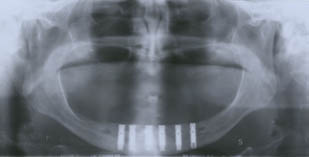

Casos clínicos resueltos con el uso del "Dispositivo Gordils".

Caso # 2.

Paciente edentulo bimaxilar.

El "Dispositivo Gordils" fue utilizado para colocar 6 implantes en el maxilar inferior.

Caso restaurado.